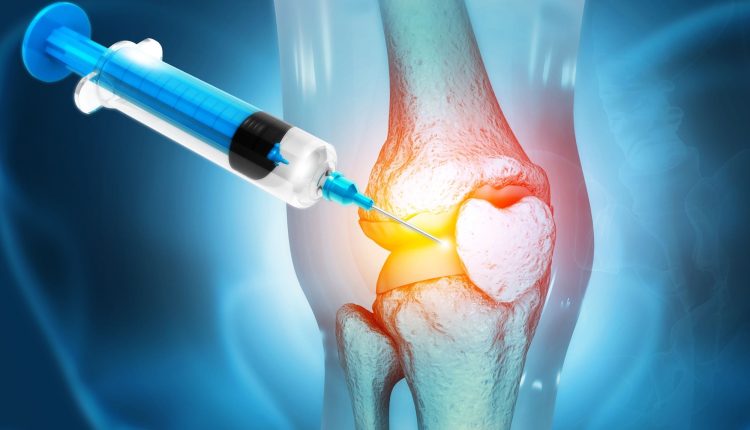

درمان با روش تزریق به زانو

یکی از انواع روشهای درمان پارگی مینیسک زانو تزریق دارو یا سایر مواد با خاصیت درمانی یا ترمیمکنندگی است. تزریق سلول بنیادی به زانوی آسیبدیده و پیآرپی دو روش نوین هستند؛ که توسط پزشکان مجهز به دانش روز و تجربه درمانهای موفق انجام میشوند. البته تحقیقات روی آنها همچنان ادامه دارد.

در درمان مینیسک پارهشده با سلول بنیادی مقداری سلول بنیادی مزانشیمی جوان بهطور متمرکز به زانوی آسیبدیده تزریق میشود. اما چگونه این سلولها به ترمیم پارگی کمک میکنند؟!

در حالت طبیعی بدن انسانها از میلیاردها سلول تخصصی تشکیل شده است؛ که بهطور مرتب فرسوده و دوباره بازسازی میشوند. سلولهای بنیادی بدن شما توانایی تبدیلشدن به انواع سلول، از جمله سلولهای بافت غضروفی، را دارند.

البته با افزایش سن تولید این سلولها در بدن کاهش مییابد و توان بازسازی بافتهای آسیبدیده کمتر میشود. با گسترش دانش علمی موجود درباره کاربردهای سلول بنیادی، امروز از تزریق سلول بنیادی در درمان آرتروز و بازسازی مفاصل هم استفاده میشود به این صورت که تزریق سلول بنیادی فرایند ترمیم غضروف را تحریک کرده و روند بهبودی را سرعت میدهد.